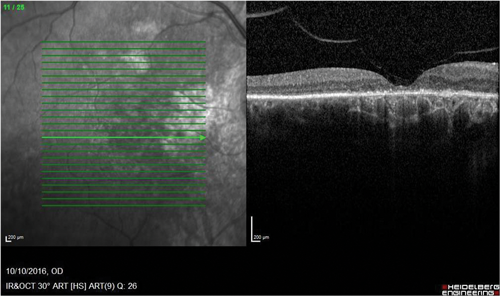

Figure 2: Consequences of chronic CSCR. (Top) Autofluorescence image of the right fundus showing widespread damage and atrophy of the retinal pigment epithelium and a ‘gravitational’ appearance. (Bottom) OCT scan of the same eye showing photoreceptor loss and RPE damage as well as abnormalities in the choroid.

Sight loss is due to photoreceptor damage and atrophy of the retinal pigment epithelium (RPE) (Figure 2). There are many different treatment options for chronic CSCR and no standard guidelines published on treatment protocols [5]. The treatment options range from systemic treatment to photodynamic therapy, as well as argon laser and micropulse laser treatment. Unlike other retinal conditions, anti-VEGF does not appear to be a useful treatment modality.